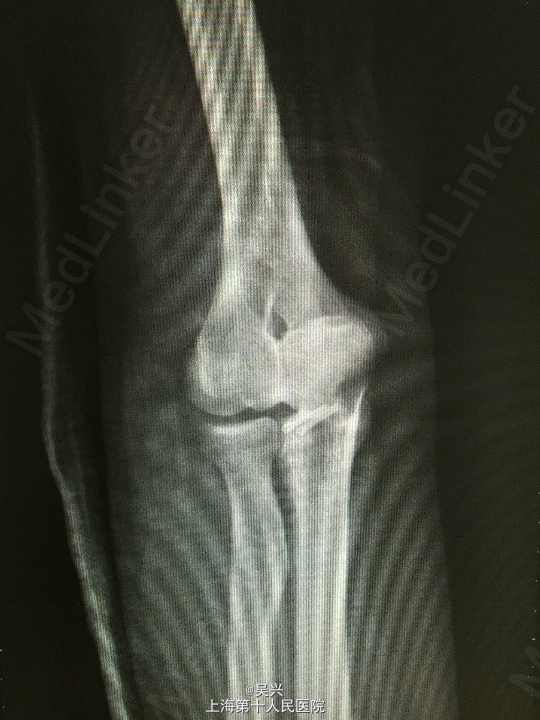

左肘外伤肿痛畸形3小时。左肘屈曲位着地受伤。

急症查体见肘关节肿胀、触痛,存在向后方半脱位及外侧松弛不稳定。

诊断:左肘恐怖三联症。 处理:术前准备,抗炎消肿治疗,术后三天行左肘正中切口显露尺骨冠状突,术中见尺骨冠状突粉碎性骨折,用两枚微型空心螺钉固定,发现屈肘位置仍有肘关节半脱位趋向。予伸肘位石膏固定,术后2周改屈肘45度位石膏固定,术后4周拆石膏,能逐渐屈肘至90度。

随访:术后1月患者肘关节稳定性良好,伸肘0度,屈肘90度,理疗辅助功能锻炼中。 讨论:肘关节脱位(半脱位)伴尺骨冠状突骨折、桡骨小头骨折称为肘关节恐怖三联症。该症存在极度肘关节不稳定,容易发生向后方、侧方脱位。一般单纯尺骨冠状突骨折极少,多伴有桡侧结构损伤和关节不稳定。肘关节恐怖三联症治疗原则一般是复位固定尺骨冠状突和桡骨小头,修复桡侧副韧带。我们术中发现固定尺骨冠状突后关节仍然不稳定,但桡骨小头因不全骨折需要石膏固定,因此不采取手术修复外侧副韧带,而是石膏固定,术后也取得较好的效果。